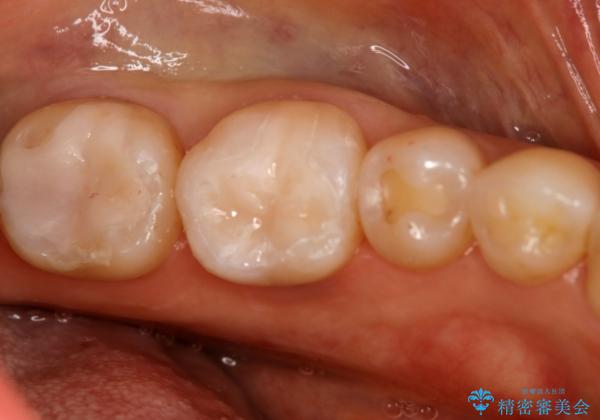

下の奥歯の銀歯を白くしたい

- 左下奥歯のメタルインレーを白くしたいと希望された患者様です。

形態、切削量などを考慮し、セラミックインレーにて治療を行いました。

メタルインレー、う蝕除去後にCRにて裏層した上で、形成・印象を行いました。